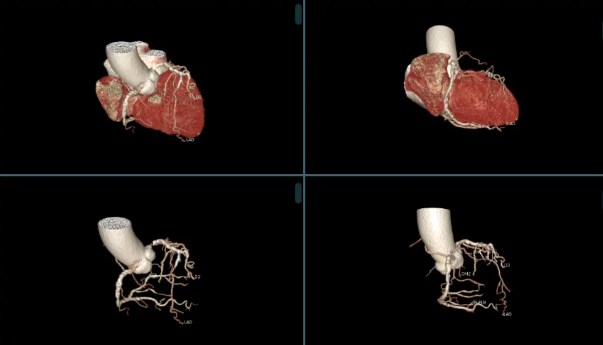

该患者因「跌倒致右髋部疼痛,伴右下肢活动障碍 1 天」至我院就诊,入院检查提示右侧股骨颈骨折。老人家既往有冠心病、高血压病史,此次入院冠脉 CTA 检查发现心脏冠状动脉多处严重狭窄。面对如此复杂的病情,手术风险极高,传统治疗策略面临巨大挑战。

考虑到患者年事已高,若选择保守治疗,长期卧床将极大增加肺炎、深静脉血栓及压疮等并发症的风险;而手术治疗则因患者合并严重冠脉病变,麻醉及手术过程中的风险显著增加。经过全面的营养支持和血压调控,心血管内科、麻醉手术中心进行了详尽的术前评估。心血管内科苏波主任医师团队先行冠脉造影术,确认冠脉严重狭窄后,立即实施了支架置入术,稳定了病情。术后当日,程建文主任医师团队紧接着进行了右侧人工股骨头置换术,手术过程顺利,术中出血量控制在百毫升左右。术后,患者被转入外科重症监护室进行密切观察,次日即转回普通病房,生命体征平稳,恢复迅速。

心血管内科苏波主任医师指出:「冠脉支架术后患者需长期服用抗血小板药物以预防血栓形成,但这类药物会增加外科手术的出血风险。通常,术前需停用双联抗板药物至少一周,但停药期间支架内血栓形成的风险依然存在。」